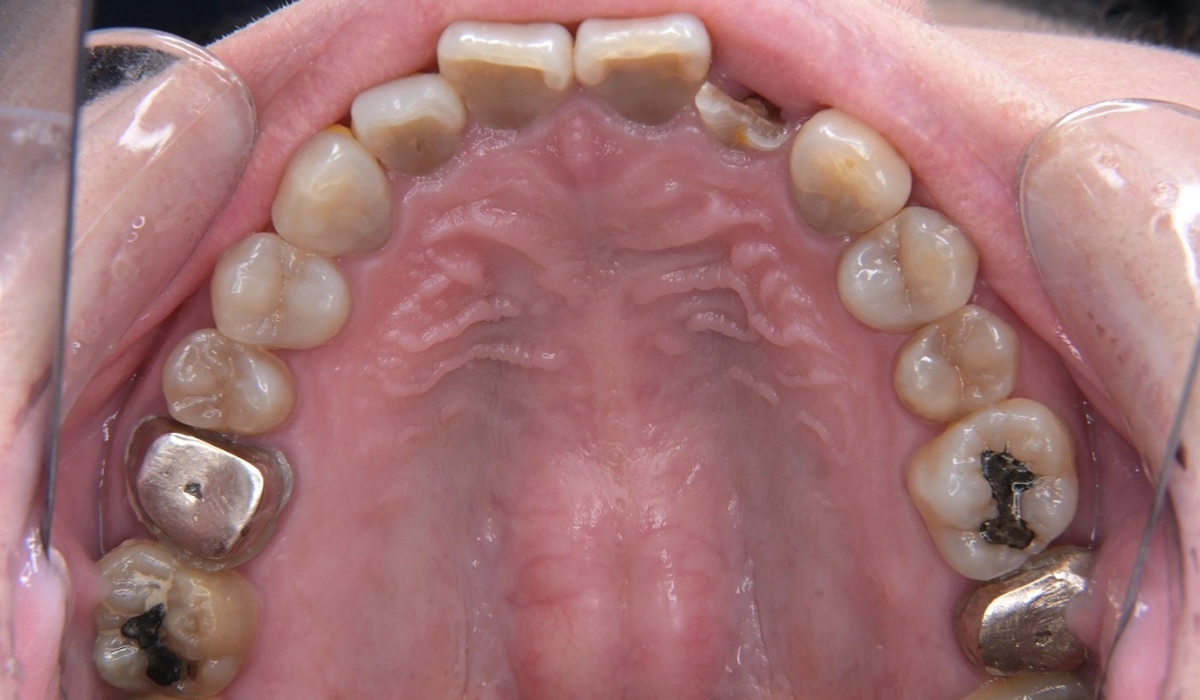

こちらが術前の口腔内写真になります。

問題点としては前歯部、臼歯部で進行したカリエスおよび前歯部歯肉増殖症、広範型慢性歯周炎StageⅡ GradeAが挙げられます。本症例では前歯部の審美性の回復について患者様との話し合いのうえセラミック修復による治療を選択しました。

治療のステップとして全顎的な歯周環境の改善のための歯周基本治療、前歯部の歯周形成外科、前歯部カリエスに対する根管治療、前歯部プロビジョナルレストレーションによる歯肉形態修正、最終補綴の順で治療を進めていきました。